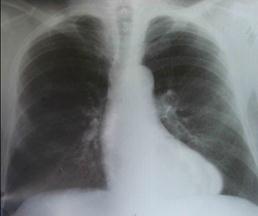

Рентгенологическое исследование.

В периоде компенсации порока незначительно увеличен левый желудочек. С развитием сердечной недостаточности происходит увеличение левого желудочка с выбуханием аорты, затем левого предсердия и, наконец, правого желудочка (рис. 8-3).

Рис. 8-3. Стеноз аортального клапана.